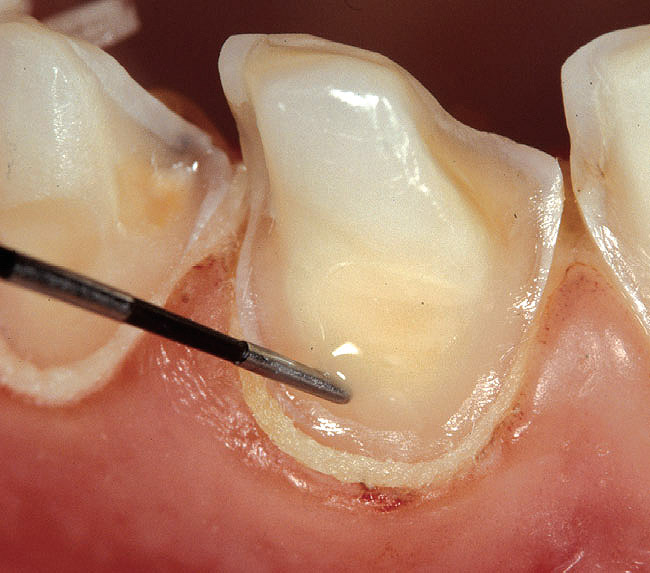

Figure 2k  The adhesive is applied  with precision using a drop of resin on  the tip of a periodontal probe. Direct contact  between the dentin and the tip of the probe  should be avoided. The probe is used to  help spread the adhesive to the edges of  the exposed dentin.

Figure 2k

Figure 2l  The adhesive is left  to diffuse along the chamfer. The tip of the  probe should not approach the margin more  than 0.5 mm to avoid pulling of the resin (red  rectangle shows a magnified view of gingival  dentin margins seen in image M).

Figure 2l

Figure 2m  Because  of surface tension phenomenon, the  adhesive spreads onto the primed dentin  surface but is arrested at the sharp edge of  the margin.

Figure 2m

Figure 2n  Because of the original deep  chamfer, the definition of the margin is not  affected by the presence of the adhesive  laye.

Figure 2n